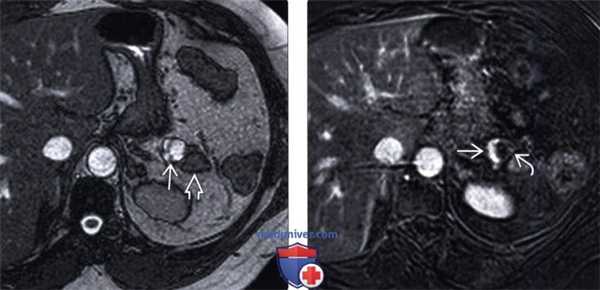

(Левый) При Т2 МРТ в режиме true FISP на аксиальной томограмме в теле поджелудочной железы определяется четко отграниченное объемное образование, содержащее два Т2-ярких компонента. Обратите внимание на нерасширенный панкреатический проток и внешне неизмененную паренхиму поджелудочной железы дистальнее опухоли.

(Правый) У этого же пациента при Т1 МРТ с контрастным усилением и подавлением жира на аксиальной томограмме в медиальной части объемного образования определяется контрастная опухолевая ткань , тогда как кистозная/некротическая латеральная часть опухоли не контрастируется.